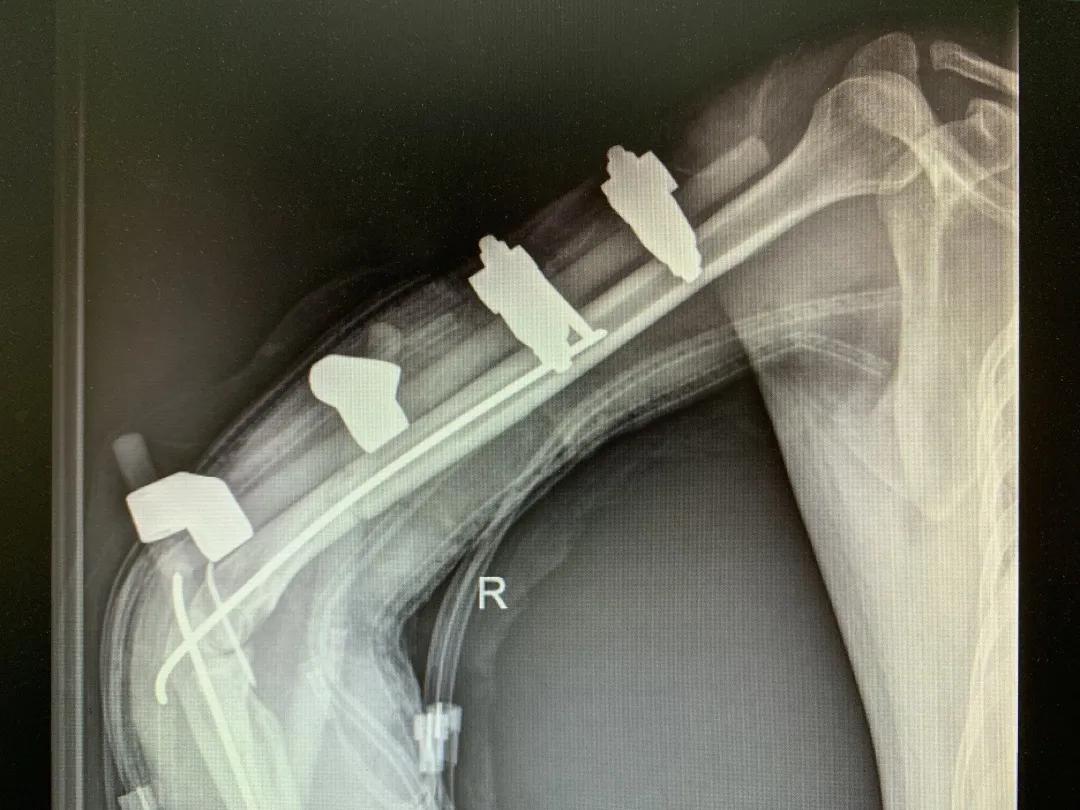

为了给患者争取抢救的时间,抢救团队通过运用球囊阻断术把球囊打到腹主动脉,临时阻断血流,在最大限度地减少血流的情况下为营救生命抢得机会,这也是日照开展的首例腹主动脉临时阻断术。即便如此,患者在整个手术过程中也输入了整整12个单位的红细胞,这就相当于人体一半的血已经丢失了。

清创、止血、接骨、将粉碎的骨块一块块拼接完整,同时给予VSD敷料负压引流。经过三次清创清除后,明确了坏死的皮肤等组织,创面好转,肉芽组织良好……